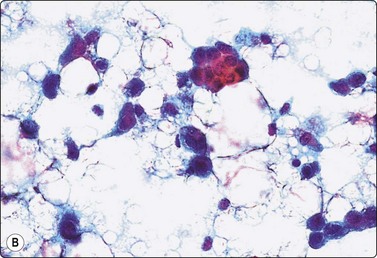

image image image

Fig. 7.8 Lactating breast

Dispersed acinar cells with abundant pale and fragile cytoplasm, rounded nuclei and prominent central nucleoli; background of lipid secretions (A, MGG, HP; B, H & E, HP oil); (C) Corresponding tissue section (H&E, IP).

Criteria for diagnosis

Cellular smears,

Poorly cohesive, mainly dispersed epithelial cells of acinar type,

Cells have abundant fragile cytoplasm with secretory vacuoles and frayed borders,

Rounded vesicular nuclei and central nucleoli,

Dirty background due to lipid secretion and stripped nuclei with prominent nucleoli,

Single bipolar nuclei difficult to find.

FNB is very useful in reducing surgical intervention to a minimum during pregnancy and lactation. The pattern seen in FNB smears of ‘lumps’ in a pregnant or lactating breast can be problematic to inexperienced eyes and cause concern for malignancy.93,94 Smears are usually cellular. The cells are enlarged and arranged in loose groups or singly. The cells have an abundant fragile cytoplasm, vacuolated and finely granular. Nuclei are round, central, larger than the usual ductular cells, and have distinct small nucleoli (Fig. 7.8B). Some epithelial nuclei are stripped of cytoplasm. Single naked bipolar/oval nuclei are difficult to find. The background of abundant milky secretion with numerous lipid droplets seen as vacuoles is characteristic of actively secreting breast tissue and is the main clue to the diagnosis (Fig. 7.8A).